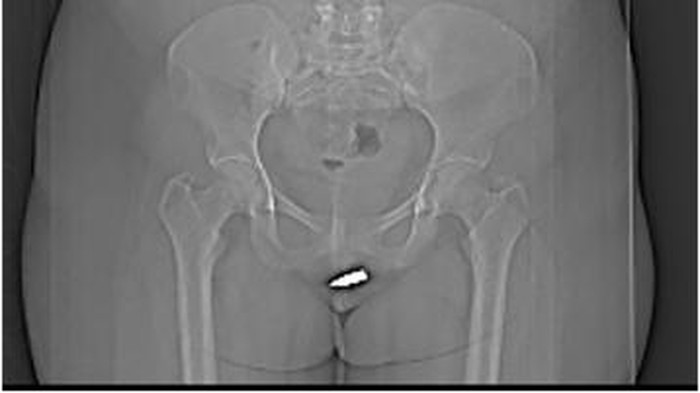

Dikutip dari laman Sciencedirect, saat pemeriksaan panggul terlihat jelas peluru tertahan di bagian tersebut. Selain dilihat dari CT Scan, peluru tersebut juga dapat terasa saat diraba secara langsung.